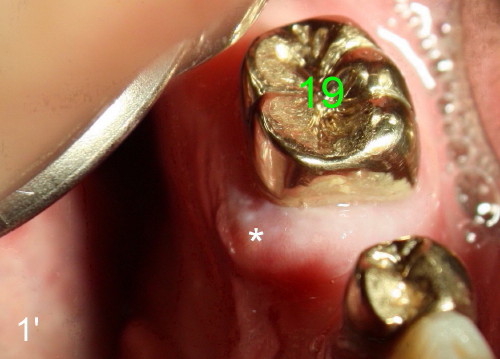

At the time of impression and design, there is no gingival swelling around the tooth #19 (Fig.1: >). This is not the case (Fig.1': *) at the appointment of implant placement on the other side (#30). Return the main text